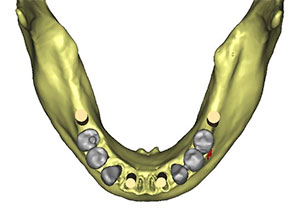

La prótesis dental híbrida es una estructura fija atornillada sobre implantes dentales que tiene como objetivo reponer las piezas dentales y tejidos blandos -encía- perdidos.

La prótesis dental híbrida consta de una estructura de metal recubierta de varias capas de porcelana blanca y rosa que dan la estética de los dientes y de la encía.

Dicha estructura se atornilla sobre los implantes que se han colocado previamente en el hueso mediante la cirugía.

Esto se hace mediante unos tornillos intermedios que fijan toda la estructura y sellan el espacio entre la prótesis y los implantes.

Por último, la entrada de estos tornillos a través de la prótesis se sella mediante el uso de teflón y resina, como si se estuviera realizando una obturación o empaste dental.

Esta estructura de metal irá recubierta de una resina compuesta de laboratorio, que es la que va a dar la estética de los dientes y de la encía rosa.